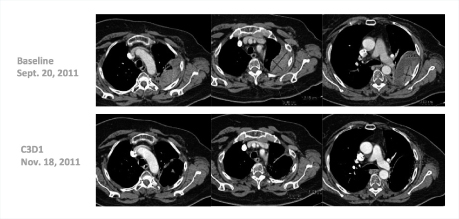

“Many of these responses have been long-lasting, with patients remaining on treatment for 20-plus weeks,” he said. Several patients have received the drug for 1 year, including a complete responder who had received 14 prior lines of treatment (Fig. 1). One patient with triple-negative breast cancer responded dramatically after 10 prior lines of treatment (Fig. 2).